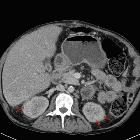

CT

- may show microcalcifications within the microcysts in the renal medulla and cortex